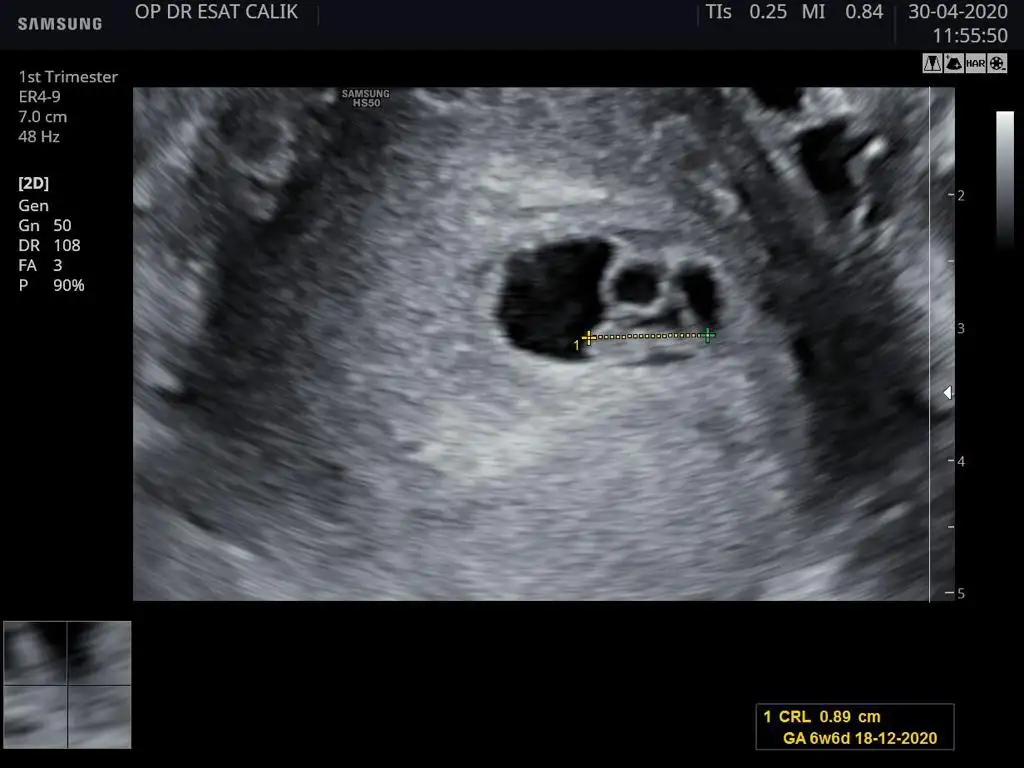

Neden kalbi durabilirmiş Allah korusun Allah sağ salim sana kavuştursunBu da benim fasulyem. Normalde sata gore 7+6 ama ultrasonda 6 haftalik cikmis. Doktor kese kucuk cocuk normal kalbi durabilir dedi. Kanama alanim var fotoda belli oluyor zaten